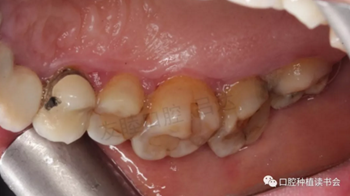

(1)初診:50歲女性患者,上頜中切牙及側(cè)切牙因齲壞缺失,植入3顆種植體;4單位聯(lián)冠完成修復(fù)。兩年后,因“種植體周?chē)つし磸?fù)水腫溢膿1個(gè)月”就診。(圖1)

圖1 初診口內(nèi)情況,可見(jiàn)種植體周?chē)つつ[脹明顯